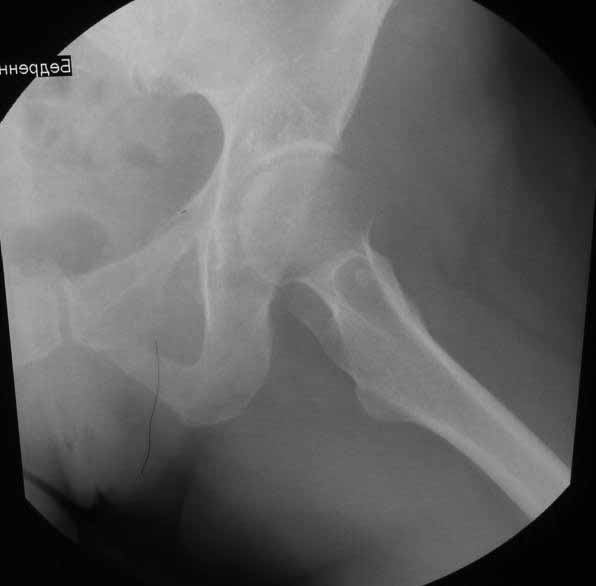

Уважаемые коллеги. Хотелось бы услышать мнения и советы по представляемому случаю.

Пациентка 45 лет. Бесцементное эндопротезирование левого тазобедренного сустава 6 лет

назад (впадина RM, Mathys, металл-металл, ножка Зульцеровская). За 10 лет до

протезирования коррегирующая остеотомия бедренной кости, которая не срослась в течение

года до удаления пластины, а затем срослась в течение 3 месяцев иммобилизации в кокситной

повязке. После протезирования получилось наблюдать пациентку почти постоянно, поскольку

через 2 года синтезировал ей лодыжки на оперированной стороне, затем, через несколько

месяцев удалил фиксаторы, а в 2009г. резецировал мениск на противоположной стороне. Боли

все эти годы не беспокоили. Пациентка чуть выше среднего роста, вес тела нормальный.

Физические нагрузки переносила хорошо. Работает на 7 этаже без лифта. Год назад экстирпация

матки по поводу лейомиомы больших размеров. Несколько месяцев назад появились боли в

области левого тазобедренного сустава. При рентгеновском и КТ исследованиях (июль с.г.)

нестабильность тазового компонента. От предложенной замены протеза пациентка на тот

момент, слава богу, отказалась. Через какое то время боли в области левого тазобедренного

сустава практически полностью прошли, а около 2 месяцев назад появилось ощущение

патологической подвижности таза и боли в паху справа, которые через некоторое время

уменьшились, а потом снова усилились после значительных физических нагрузок (много ходила

по песку на пляже, носила тяжести). Ежедневно принимала диклофенак. На рентгенограммах

переломы правой лонной кости. Сейчас госпитализирована из-за болей в паху справа. Боли

слева не беспокоят. На фоне снижения нагрузок в стационаре боли значимо уменьшились.

-Если думать о ревизии, то когда? На представленных снимках тазобедренный сустав до и

сразу после операции, затем 2 снимка 2009г., когда ничего не беспокоило, затем КТ 2-х

месячной давности и вчерашние рентгенограммы обоих тазобедренных суставов.